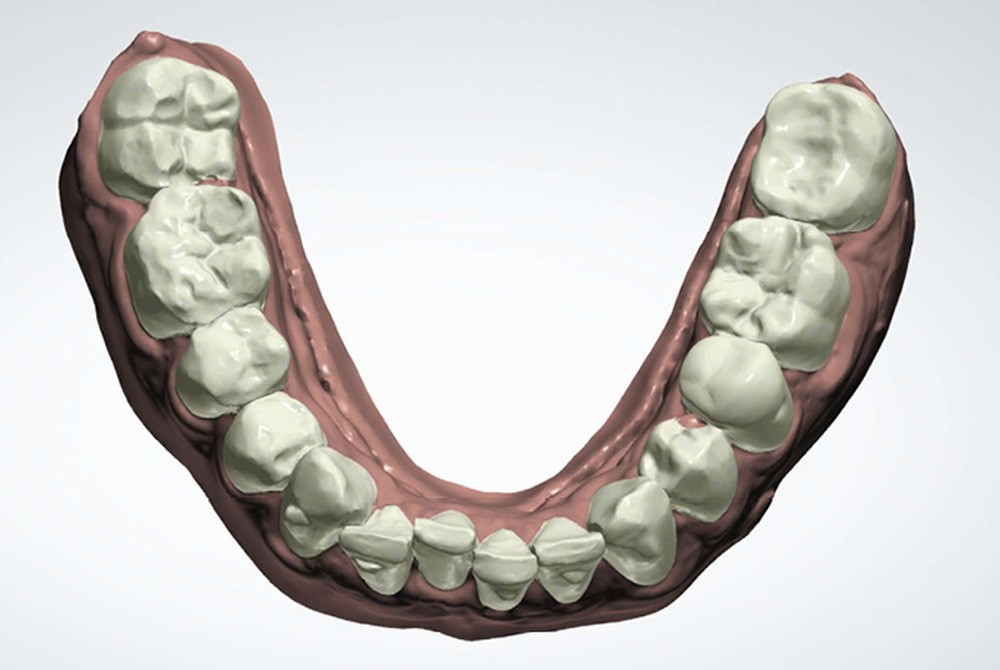

Le plan de traitement établi conjointement avec son chirurgien-dentiste traitant consiste à réaliser un alignement dentaire mandibulaire et à réaliser des extractions de 16 et 15 pour un remplacement par prothèse implanto-portée.

La durée orthodontique prévue est de neuf mois, avec comme contrainte principale l’absence de possibilités de modification des formes d’arcades.

Le gain de place se fera par des réductions interproximales sur la zone incisivo-canine mandibulaire.

Il est décidé de ne pas redresser la 43 complètement afin de ne pas entraîner d’interférences occlusales.